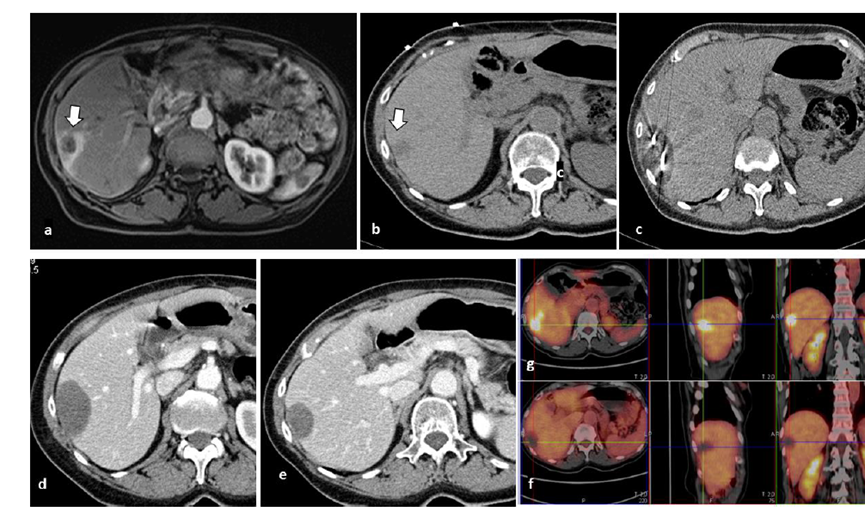

79 岁男性,肝转移(结直肠癌)肿瘤的完全消融病例

( a ) 轴向 MRI 和 ( b ) 轴向 CT 显示肝S8段有一个16mm的病灶,邻近肝缘。( c )冷冻消融期间CT显示放置了2个冷冻探针,低密度冰球包围病灶。(d)术后1个月随访 CT显示冰球对应的坏死区域,未见复发。(f)与基线影像(g)相比,12个月后的FDG-PET/CT显示未见FDG摄取。

(a)轴向CT显示病变位置毗邻心脏和上腔静脉(黑色箭头)。1个月后的轴向(e)和冠状位(f)增强CT扫描显示低密度区域,由于肉芽组织反应引起的边缘增强。